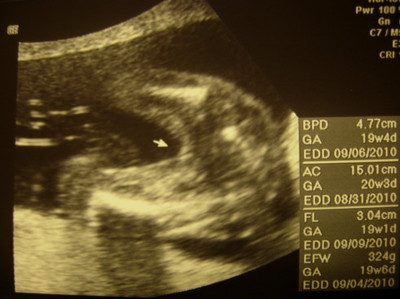

(圖/懷孕週期:19W)

醫生說照片上的箭頭,可以推斷你是「妳」。馬麻問把拔:「果真如你的願了,很開心吧?」其實開心也只是一下下而已。把拔開始要擔心,未來妳的門禁時間要設幾點、怎麼應付那些打電話來找妳的臭男生、萬一妳晚歸怎麼辦、我是不是該等門、等門時要佯裝笑容還是手持「家法」……。現在想這些太早喔?未雨綢繆一下嘛!